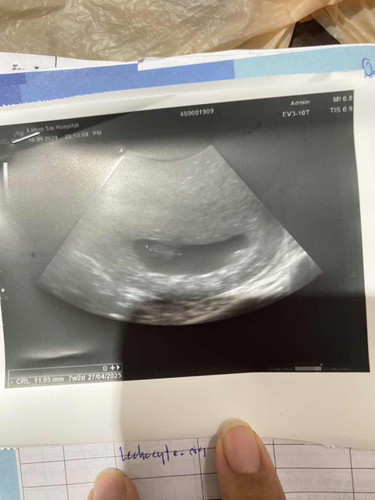

แม่ๆค่ะหมอบอกว่าน้องไม่เจริญเติบโตไม่เห็นหัวใจ น้องยังอยู่ไมค่ะ🥺10 w